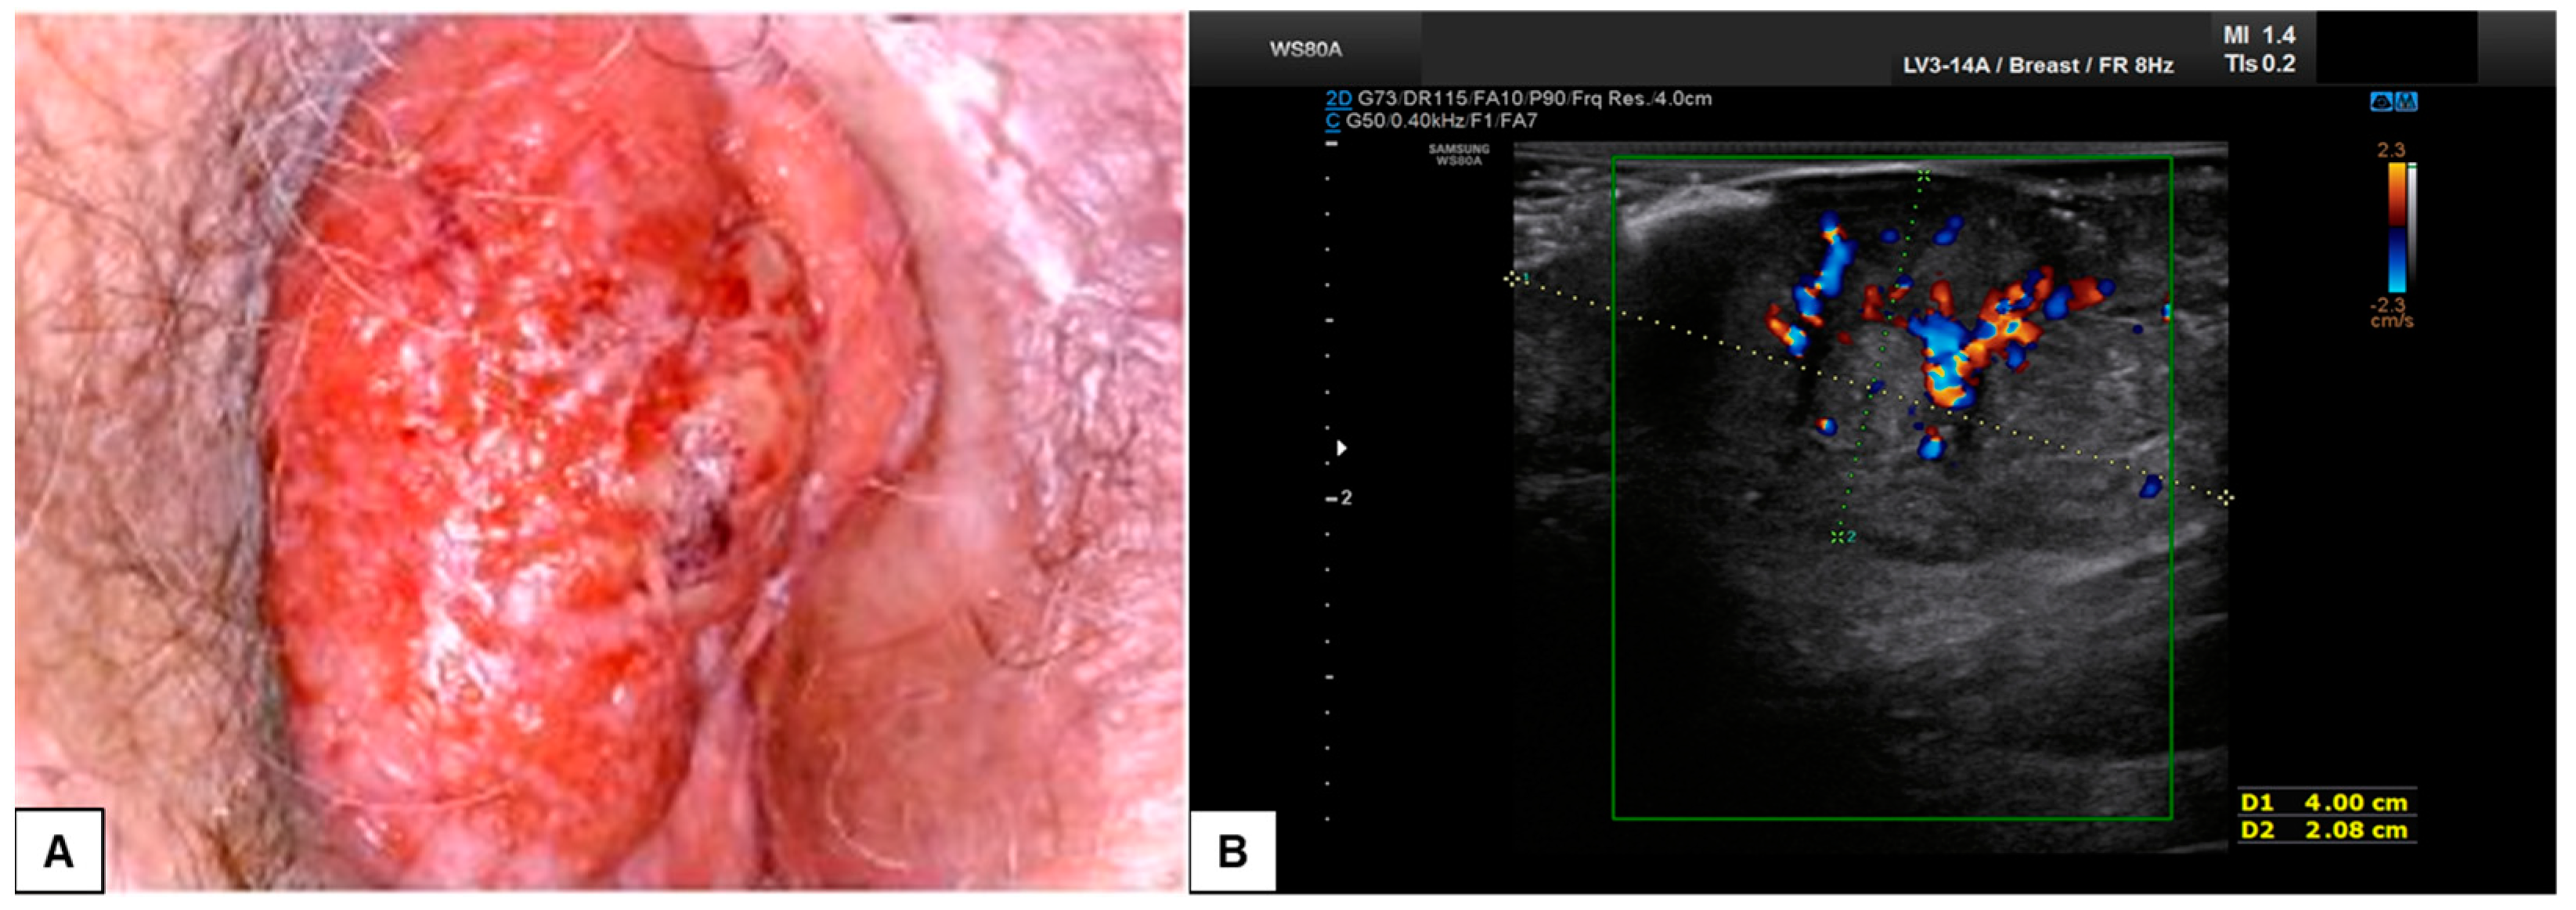

7.3. Malignant Vulvar Lesions

- Measurement from the adjacent most superficial dermal papilla to the deepest point of invasion

- Measurement from the basement membrane of the deepest adjacent dysplastic (tumor-free) rete ridge to the deepest point of invasion, which should be the technique of choice. Because epidermal ridges cannot be distinguished on ultrasonography, our suggestion is to take the lower hyperechogenic line of the epidermal layer as a reference (Figure 10).